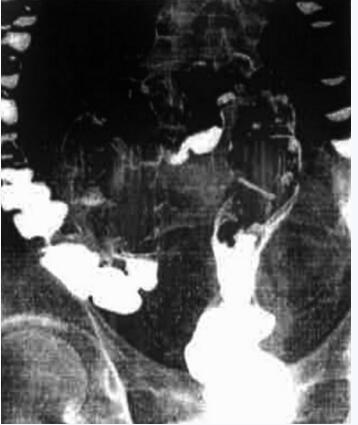

全消化道造影:直肠、乙状结肠拉长伸直(图46-3)。

图46-3 全消化道造影